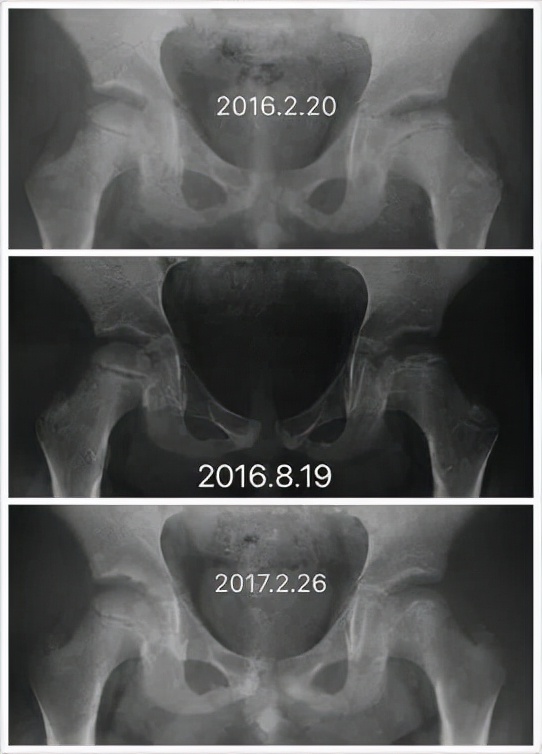

Perthes病即 儿童股骨头特发性缺血性骨软骨病,于1910年被Legg、Calve、和Perthes三位学者总结报道,因此也称为Legg-Calve-Perthes病,简称LCPD。发病早期,患儿往往出现跛行和患侧大腿中下段的疼痛不适、有时甚至是健侧膝盖周围疼痛,休息几天就可以缓解。但由于儿童天性活泼好动,上述症状常常容易复发。因此好多孩子常常被家长乃至初诊医生忽视、只是简单认为是“滑膜炎”、“缺钙”或者所谓“生长痛”,没有早期发现并且及时确诊、科学施治,而遗留了头臼曲率适应不佳、髋臼覆盖不良、股骨近端形态异常等等生长发育畸形(图1),导致髋关节出现软骨磨损继而早发骨性关节炎,从而严重影响日常生活和工作。而如果能够早发现早治疗,LCPD完全可以获得优良结果乃至正常髋关节状态(图2)!

图2 LCPD患者影像学变化